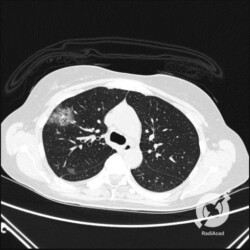

Os agentes etiológicos infecciosos são variados (bactérias, vírus, fungos, parasitas…), mas o que ocorre nos pulmões durante uma infecção por qualquer tipo de agente é a substituição do ar alveolar por secreção (pus, muco, eventualmente sangue ou necrose…) e com isso a manifestação radiográfica vai ser a mesma já que todas estas secreções apresentam a mesma densidade radiográfica: partes moles.

E o nome dado a esta alteração radiográfica que corresponde à substituição do ar alveolar por líquido é a consolidação alveolar.

Uma consolidação alveolar é, por definição, uma opacidade (imagem densa, branquinha) homogênea ou às vezes heterogênea (pela presença de calcificações ou cavidades), de limites mal definidos, exceto quando toca a pleura da parede ou das cissuras pulmonares. É um termo usado tanto em radiografia, como em tomografia computadorizada. Na tomografia, um outro termo é usado: vidro fosco, que é uma opacidade (branquinha mas não tanto como a consolidação), que borra o pulmão mas deixa ver os vasos de permeio (igual bigode de adolescente: dá pra ver todo o fundo).

Nós vamos mostrar aqui um pequeno apanhado de pneumonias de variados agentes, em diversos segmentos e lobos pulmonares, com extensões variadas. O objetivo é identificar o padrão radiológico de consolidação alveolar e não determinar o agente infeccioso, isso vai ser assunto para mais adiante. Aliás já antecipo que é fundamental saber localizar a lesão, porque alguns destes bichos gostam de determinados segmentos, alguns tumores também têm as suas preferências, então localização é fundamental. Se localização não fosse importante, um apartamento na beira do mar sairia o mesmo preço de um apartamento de frente pra BR-101, concordam?